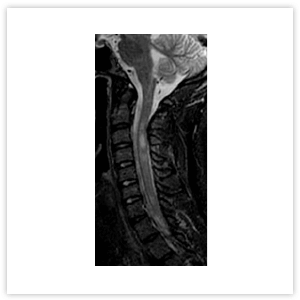

Различается и МРТ-картина заболеваний. Так, при РС в спинном мозге определяются единичные или множественные очаги, протяженностью 1–2 позвоночных сегмента, расположенные в белом веществе спинного мозга, которые обычно не распространяются на центральные отделы (Рисунок 2). При оптиконевромиелите на МРТ очаг поперечного миелита имеет, как правило, протяженность 3 и более сегмента, может распространяться на ствол головного мозга, характеризуется признаками выраженного отека, расположен в центре и заполняет более половины поперечника спинного мозга (Рисунок 3).

Рисунок 2. МРТ шейного отдела позвоночника и спинного мозга пациента с РС. Множественные очаги гиперинтенсивного сигнала, расположенные в белом веществе спинного мозга, протяженностью 1–2 позвоночных сегмента